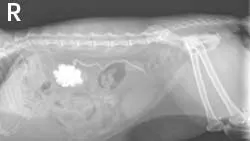

Static left renal disease and mild hydronephrosis of the right kidney with proximal hydroureter were evident on renal ultrasonography (Figure 3, right: Ultrasound of the right kidney showing pelvic dilation. View larger image). Renal calculi were present bilaterally.

Featured Image

Repeat ultrasonography and right-sided pyelocentesis with contrast confirmed right-sided hydronephrosis and hydroureter with no contrast progressing into the urinary bladder (Figure 4, above: Pyelogram identifying hydronephrosis of the right kidney and proximal hydroureter. Contrast material does not progress into the urinary bladder. View larger image). A ureterolith associated with the hydroureter was also visualized (Figure 5, below: Ultrasound identifying dilation of the right ureter associated with a ureterolith. View larger image).